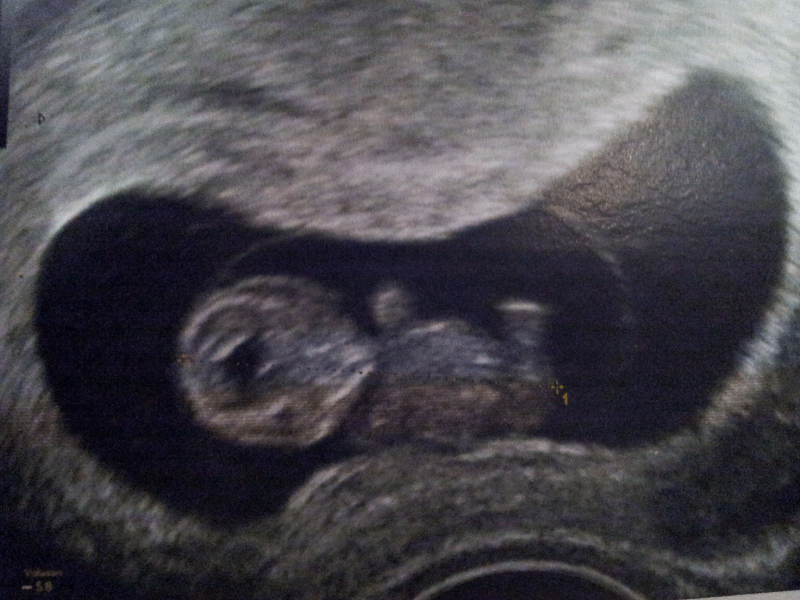

Et voila mes echos d'hier a 9SA +2jours!!

C'etait incroyable!!un mini bébé de 2cm et demie!

On a pu entendre son coeur le voir battre.

Il m'a meme fait une echo 3D!!! C'etait hallucinant!!on voyait ses petit doigts,ses pieds et son visage trop trop beau!!!Mais j'ai pas eu les images:-(

Tout va bien!!